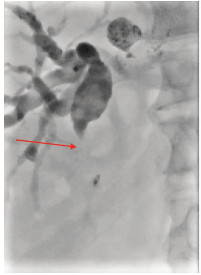

Anti-PD-1 monoclonal antibody combined with apatinib in treatment of rare primary squamous cell carcinoma of the liver: A case report

Yuchen FEI, Donglai LYU

2021, 37(3): 670-672. DOI: 10.3969/j.issn.1001-5256.2021.03.032

Abstract(870) HTML (228) PDF (2972KB)(48)

Abstract: